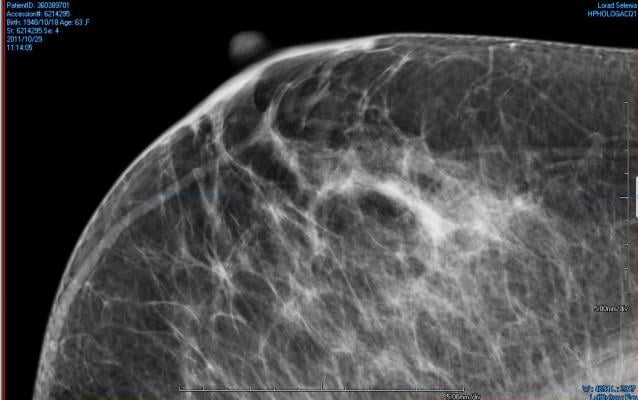

February 18, 2014 — Senates in Missouri (SB 639) and the state of Washington (SB 6050) have both advanced Breast Density Inform bills. The bills are now headed to their respective Houses of Representatives. Rhode Island has also introduced a Breast Density Inform bill (H7341). If passed, these states will join 14 others that have enacted laws regarding breast density inform. Those include: Alabama, California, Connecticut, Hawaii, Maryland, Nevada, New Jersey, New York, North Carolina, Oregon, Pennsylvania, Tennessee, Texas and Virginia.

Nationally, a Breast Density Reporting amendment is scheduled as a 2014 “Notice of Proposed Rulemaking.” That amendment would apply to the Mammography Quality Standards Act (MQSA) passed in 1992. Reps. Rosa DeLauro (D-CT) and Steve Israel (D-NY) introduced The Breast Density and Mammography Reporting Act of 2013 (HR3404).